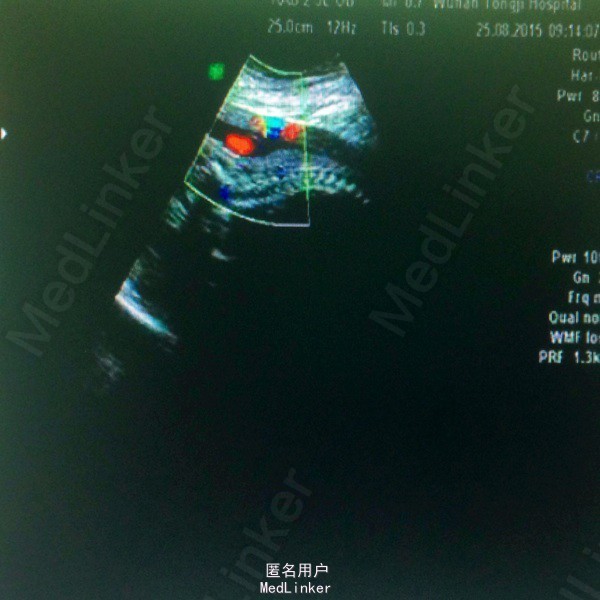

主诉:孕28周3天,彩超示双胎输血综合征 现病史:26岁女性患者,平素月经规律,现孕28周3天,昨日外院查B超提示双活胎,羊水量极多,B胎儿全身皮肤及内脏、脐带水肿,S/D比值偏高,考虑双胎输血综合征可能,今来我院复查B超提示,A胎儿存活,B胎儿停滞发育,A胎儿相当于28周2天,B胎儿相当于29周2天,I级胎盘,羊水多,收入院。

体检:腹隆,肝脾肋下未触及,双下肢水肿+,宫高43cm,腹围112cm,FHR130bpm,未及宫缩,骨盆外测量23-27-19-9 辅助检查:B超结果如现病史中所述,具体见图